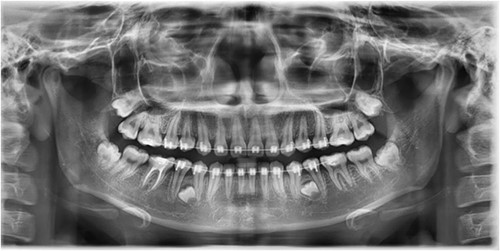

In this context, a buccal approach using a Neumann full-thickness flap was preferred (Fig. 4). When a buccal approach is planned, then the location of the mental nerve must be identified to avoid any post-operative sensory problems. The most challenging part is to exercise extreme caution during Ostectomy to avoid damage to the adjacent tooth roots.